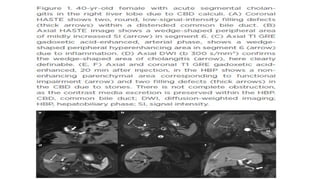

• The typical MR cholangiographic features include diffuse, multifocal short segmental

strictures and mild dilatation in the intrahepatic and extrahepatic bile ducts alternating with

normal ducts, which sometimes produce “beaded” appearance .As the fibrosis progresses and

strictures worsen, the peripheral bile ducts are obliterated and become poorly visualized on

MR cholangiography showing a “pruned tree” appearance . Diverticular outpouching of bile

ducts is another characteristic finding that occurs in up to 27% of the patients with PSC

(Almost half of patients with PSC have some degree of mural irregularity causing a shaggy or

nodular appearance of the bile ducts . PSC commonly involves both intrahepatic and

extrahepatic ducts in 75% of patients, whereas involvement of only the extrahepatic bile duct

is uncommon (10% of patients) and isolated involvement of the intrahepatic bile ducts is

reported in 15% of patients

• Abdominal ultrasonography (US) is generally non-diagnostic, although thickened or focal

dilated bile ducts are observed in PSC patients. Computed tomography (CT) demonstrates

alternating narrowing and dilatation of the bile ducts with contrast enhancement in PSC . CT

and MR imaging also show associated parenchymal changes of the liver, as well as ductal

changes in PSC. A rounded liver appearance is observed due to hypertrophy of the caudate

lobe and atrophy of the left lateral and right posterior segments in PSC .

• In PSC, T2-weighted MR images show a wedge-shaped or reticular heterogeneous area of

high-signal intensity with peripheral distribution .